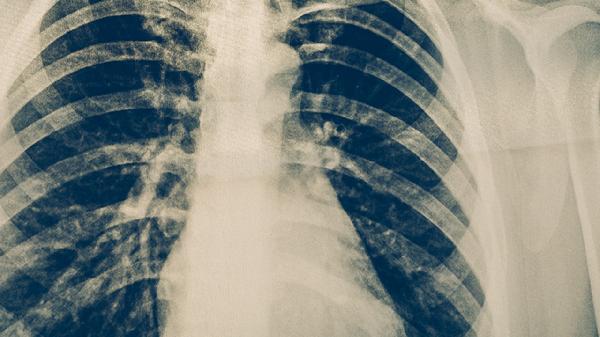

肺结核患者用药期间应保持高蛋白饮食如鸡蛋、鱼肉,补充维生素B族和维生素C。避免饮酒加重肝损伤,服药后多饮水促进药物代谢。出现持续发热、皮肤黄染或严重皮疹时须立即复诊,不可自行调整用药方案。规律作息与适度运动有助于增强药物耐受性,治疗全程需配合医生完成痰菌检查和影像学随访。